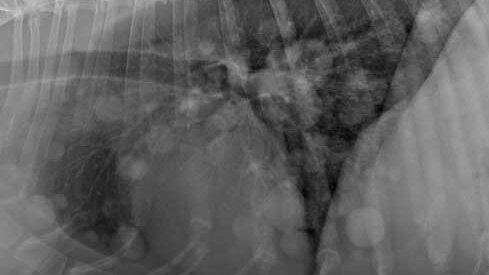

Волонтёры готовились увидеть на рентгене у собаки метастазы, но только не это